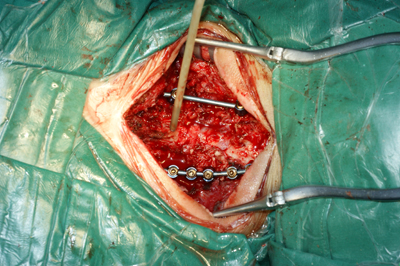

术中